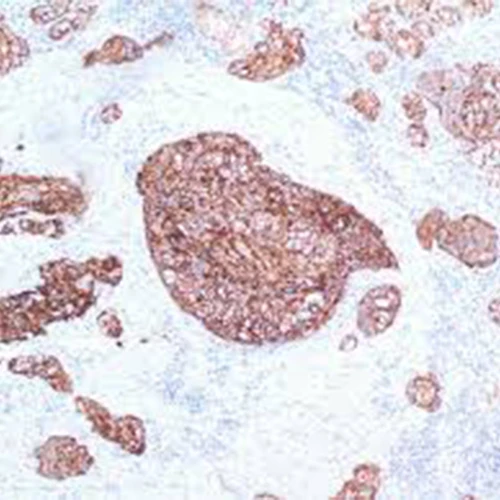

| Dilution | 1:50 |

| Staining | Cytoplasm |

| Control tissue | Tissue section from chromophobe carcinoma of the kidney |